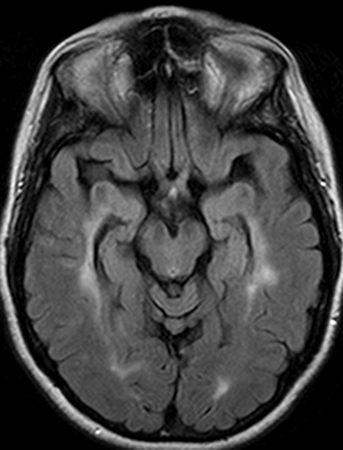

Na NO aguda, a RNM com realce por gadolínio mostra lesões com realce no nervo óptico. O nervo óptico pode mostrar vários graus de edema.[22] Quando no contexto de EM, lesões hiperintensas típicas na substância branca do parênquima cerebral, com uma localização predominantemente periventricular, podem refletir o diagnóstico estabelecido de EM. Quando essas lesões são observadas em um paciente cuja NO é o primeiro evento neurológico (SCI), existe um risco considerável de recorrência e, portanto, conversão para esclerose múltipla clinicamente definitiva (EMCD).[Figure caption and citation for the preceding image starts]: Ressonância nuclear magnética (RNM) transversa mostrando lesões típicas hiperintensas periventriculares da substância branca no parênquima cerebralDo acervo pessoal de Dra. Cris S. Constantinescu e Dr. Thomas M. Bosley [Citation ends].